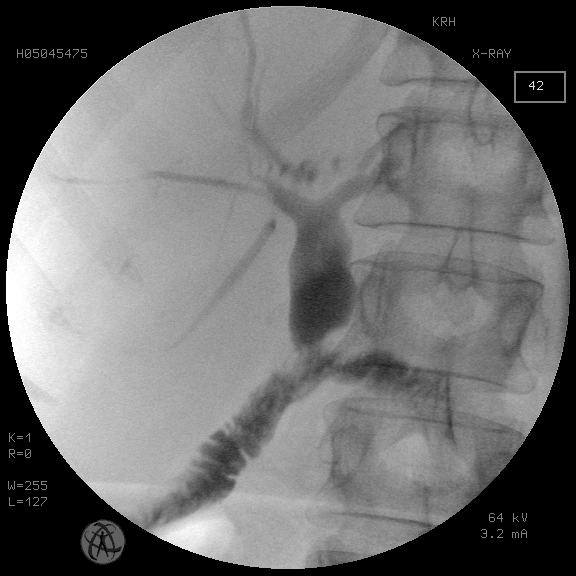

Рис. 5. То же наблюдение. Антеградная холангиография после устранения холелитиаза и стриктуры БДА

Fig. 5. The same observation. Antegrade cholangiography after elimination of cholelithiasis and stricture of the BDA

Группу исследования составили 16 пациентов со стриктурами БДА, осложненными холелитиазом. В трех случаях удалось низвести конкременты общего печеночного протока в отводящую кишку после баллонной дилятации стриктуры БДА. В 13 наблюдениях при мегахолелитиазе потребовалась этапная модификация пункционного холангиостомического доступа в чрескожный рентгенохирургический доступ диаметром 9 мм для последующей контактной механической и пневматической литотрипсии и литоэкстракции (рис. 1–5).

Случаи сочетания рубцовой стриктуры БДА с холелитиазом рассматриваются отдельно. Традиционно холелитиаз, осложняющий стриктуру БДА, рассматривается как фактор, предполагающий хирургическую реконструкцию анастомоза. Тем не менее необходимо отметить, что факт наличия конкрементов проксимальнее зоны БДА еще не является основанием для безусловного отказа от использования рентгенохирургических методик разрешения холелитиаза. Как показали результаты использования антеградного чреспеченочного доступа в желчное дерево с последующей контактной литотрипсией у пациентов группы исследования, полное освобождение желчного дерева от конкрементов было достигнуто у всех больных. При этом использовалась экстремальная модификация первичного холангиостомического доступа до 30 Fr для последующих внутрипротоковых манипуляций с ригидным перкутанным нефроскопом под операционный кожух 24, 26 СН с контактной пневматической литотрипсией (см. рис. 1–5). Такая методика используется нами более 20 лет и зарекомендовала себя не только эффективной, но и безопасной при условии бесконфликтности первичной чреспеченочной пункции желчного дерева [Охотников и др., 2011; Охотников и др., 2012].